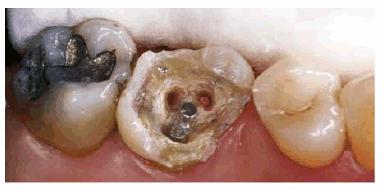

Figur 323s1823d e 18-12C: Tooth #14 after successful root canal treatment.

Figur 323s1823d e 18-12D: Removal of temporary restorative material and remaining amalgam. Gutta-percha from the pulp chamber was removed for core retention.

Figur 323s1823d e 18-12E: Completed core build-up on tooth #14.

Figur 323s1823d e 18-12F: Completed crown preparation on tooth #14.